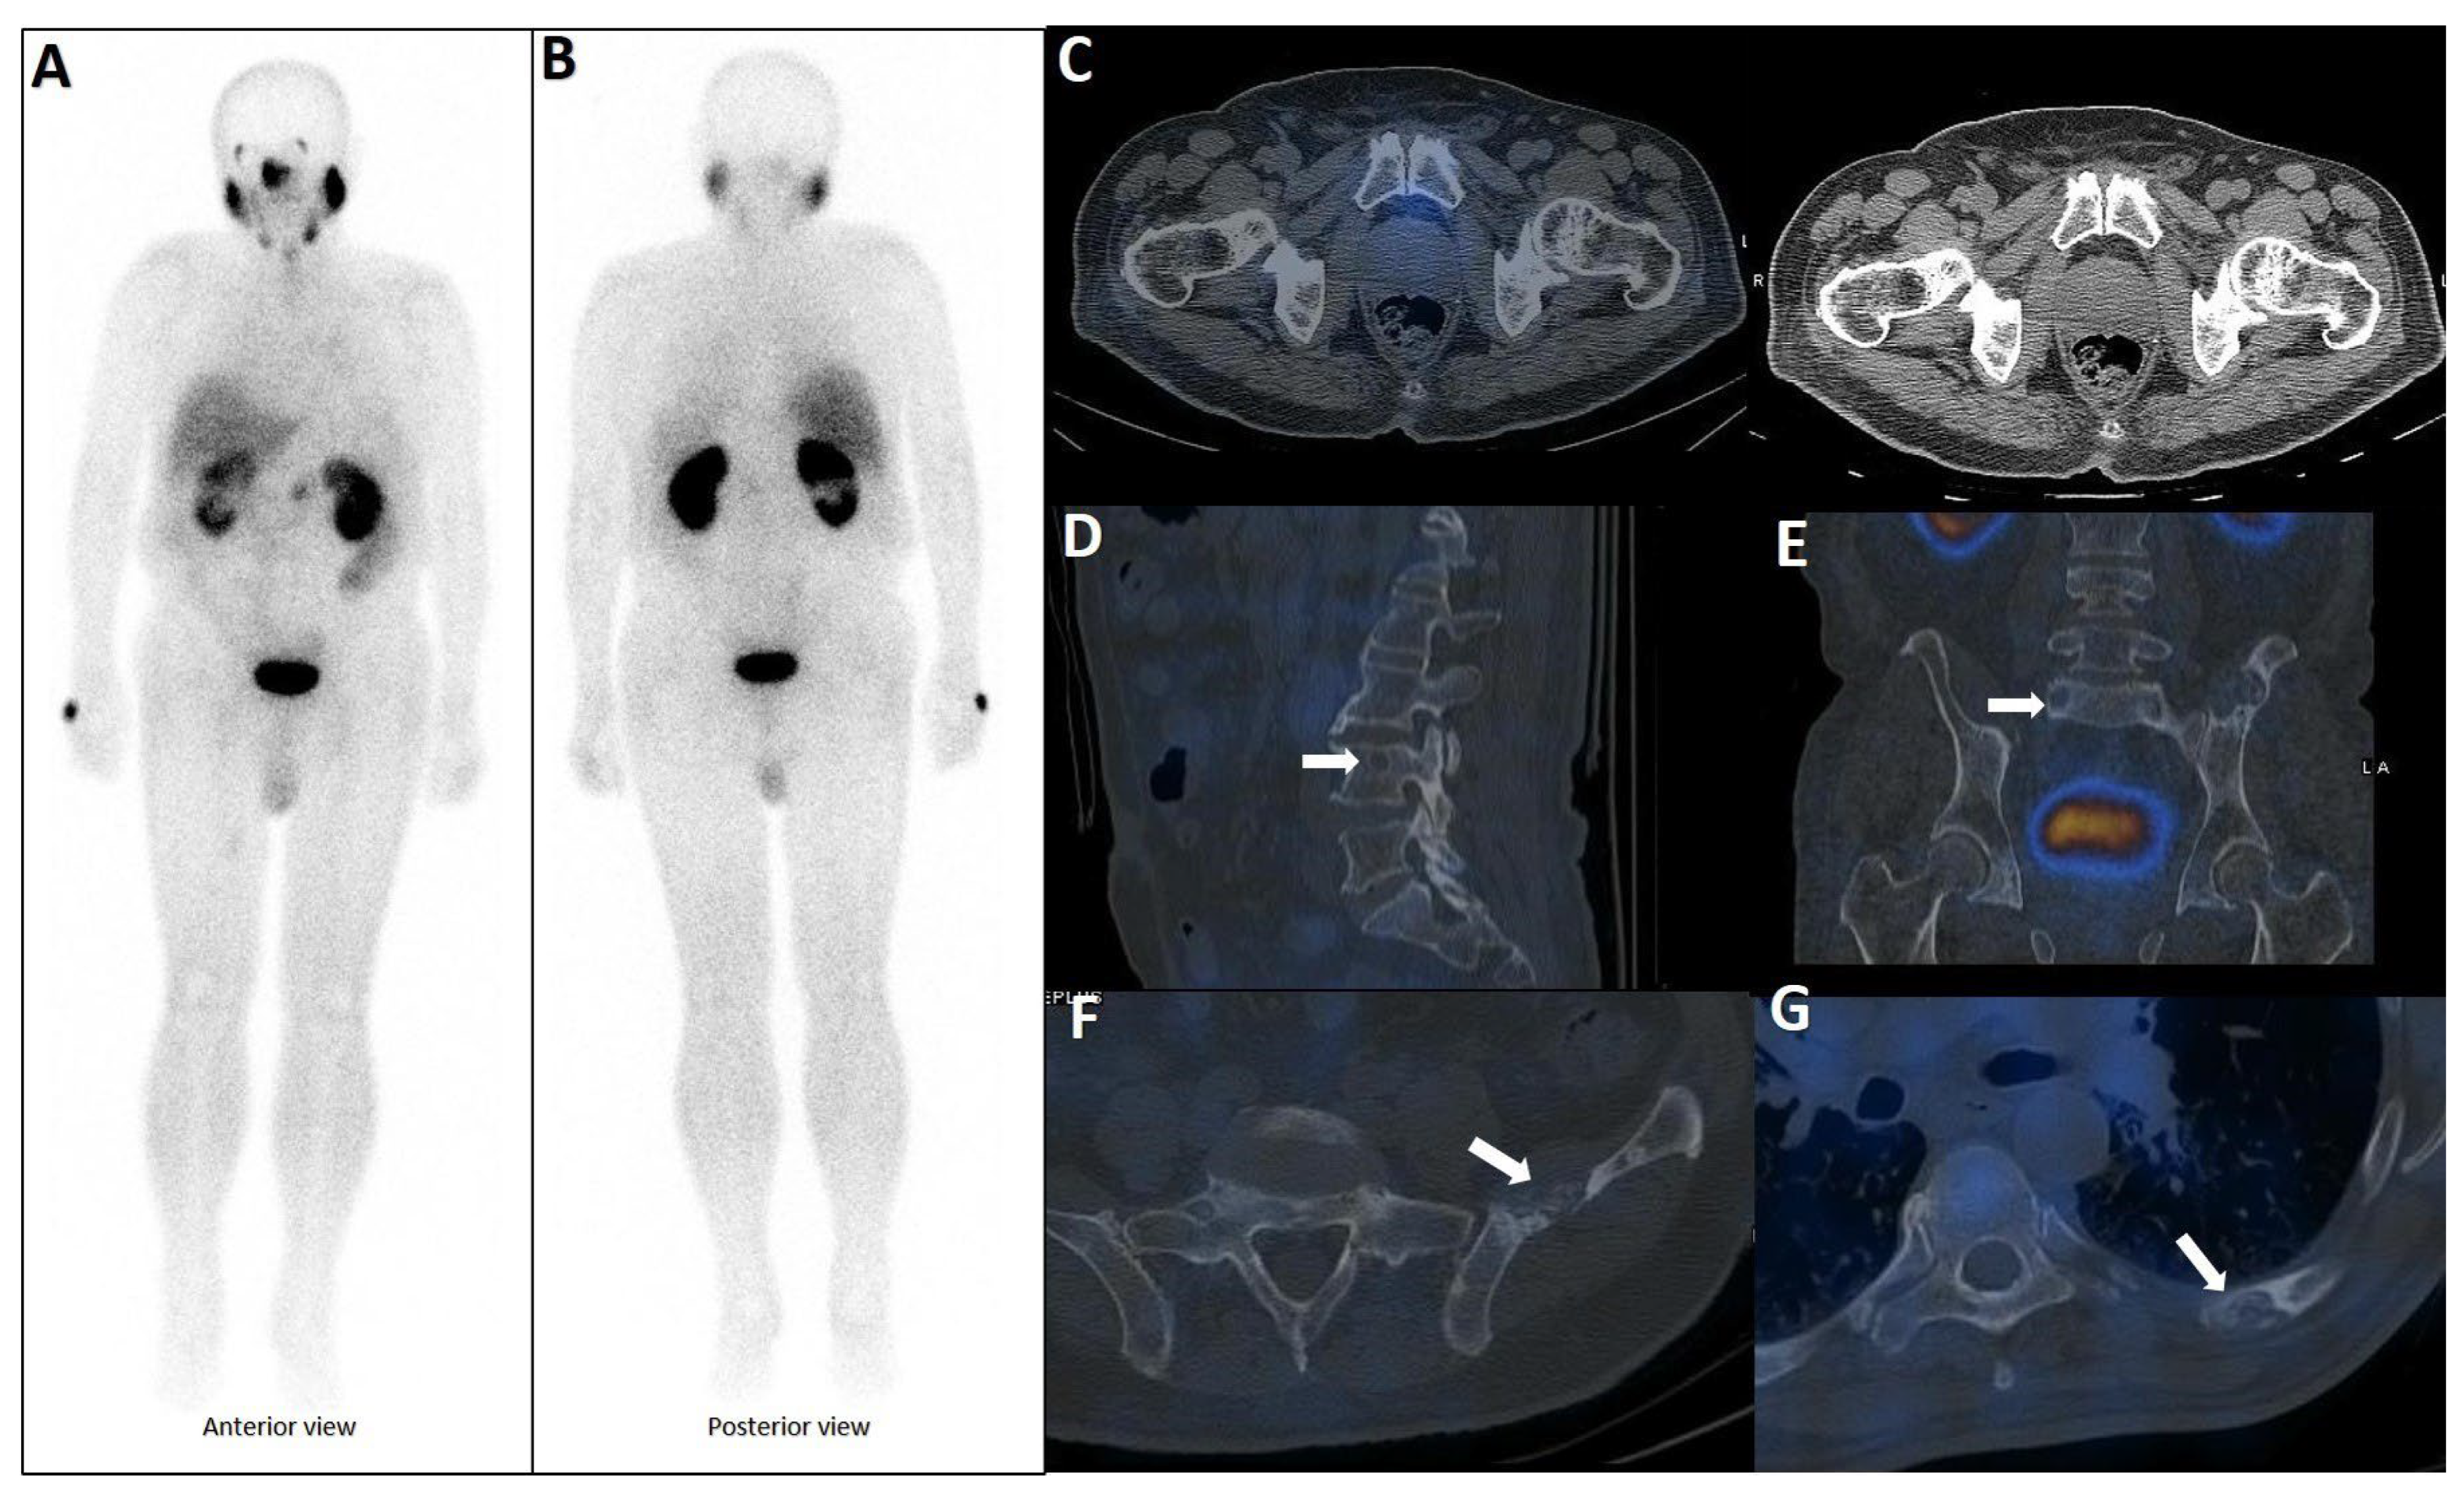

| Diagnosis * | Radiologic Appearance | References (Intense Uptake) ** |

|---|---|---|

| Prostate Carcinoma Metastasis (including Bone Metastases) | Lytic or sclerotic lesion, often multiple; may show osteolytic, osteoblastic, or mixed patterns; soft-tissue mass in some cases; aggressive appearance with cortical disruption | [7,12,13,26,40,46,47,48,49,50,51,52,53,54,55,56,57,58,59,60,61,62,63,64,65,66,67,68,69,70,71,72,73,74,75,76,77,78,79,80,81,82,83,84,85,86,87,88,89,90,91,92,93] ([50,53,66,68,77,78,81,85]) |

| Rib Fractures | Subtle cortical disruption, sclerosis, fracture line with callus formation, “pearls on a string” pattern in some cases | [7,13,40,46,91,92,93,94,95,96,97,98,99,100] |

| Fibrous Dysplasia | Ground-glass matrix, sclerotic border, expansile appearance with cortical thinning, cystic areas, intact bone borders | [7,12,13,40,42,93,101,102,103,104] ([101,104]) |

| Degenerative Changes/ Unspecific Benign | No significant morphological changes, non-specific lytic lesion with reactive changes, or normal bone tissue on CT | [13,92,93,105,106,107,108] |

| Paget Disease | Cortical thickening, irregular trabecular pattern, heterogeneous internal components | [92,93,109] |

| Osteoblastic Metastasis | Sclerotic lesion with osteoblastic features, often corresponding to tracer uptake | [58,78] ([78]) |

| Myelodysplastic Syndrome | No lytic or sclerotic changes, focal increased uptake mimicking metastasis | [12,110] |

| Fibrous Cortical Defect | Small hypoattenuating lesion with well-delimited sclerotic borders | [111] |

| Post-Traumatic Rib Lesion | Post-traumatic changes with faint uptake, no significant morphological changes | [96] |